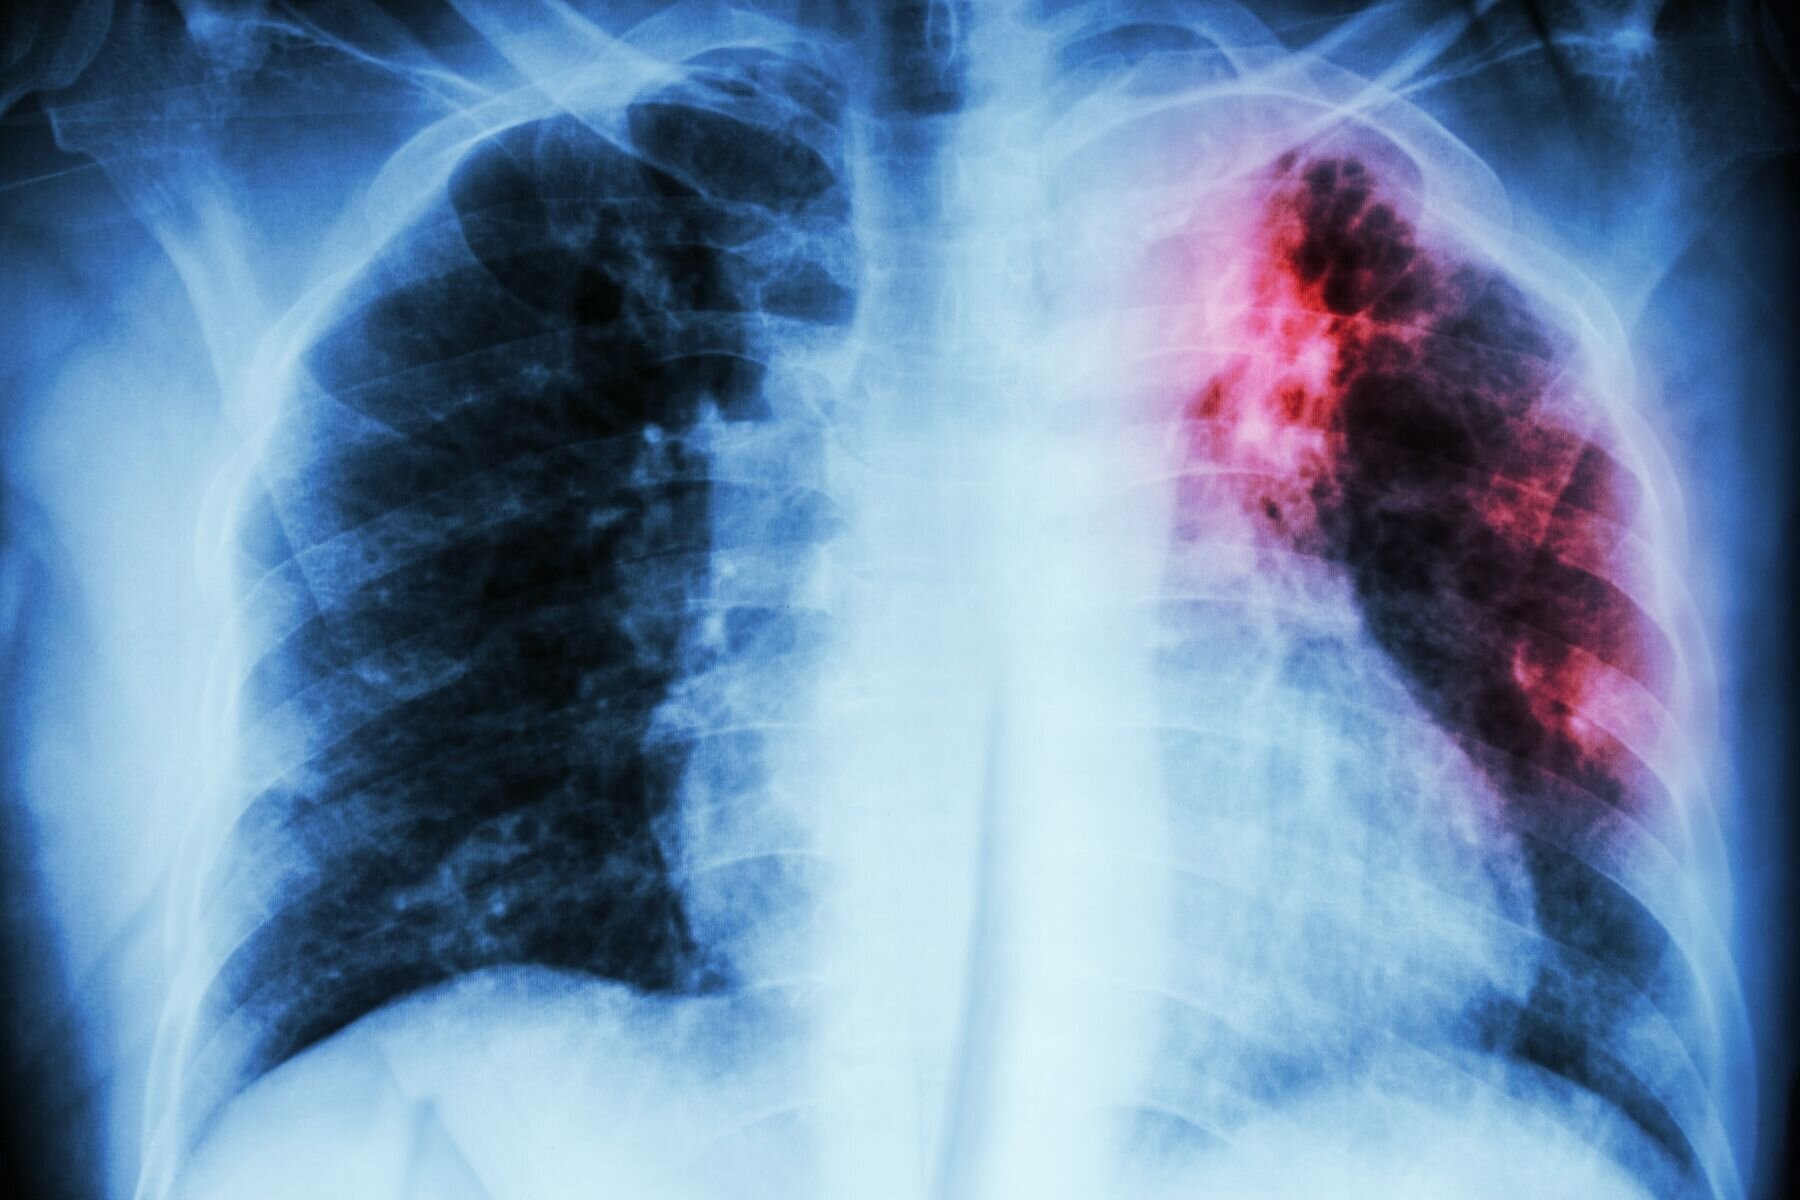

Historisk lav forekomst av tuberkulose i Norge

I 2023 var det 153 personer som ble syke av tuberkulose i Norge. Dette er det laveste antallet siden rapporteringen startet i 1962.

Selv om dette er det laveste antallet innrapporterte tilfeller siden rapporteringen startet i 1962, er det samtidig en økning i antall personer med multiresistent tuberkulose, med 15 innrapporterte tilfeller i 2023. Berild uttrykker bekymring for økningen både i Norge og på verdensbasis.